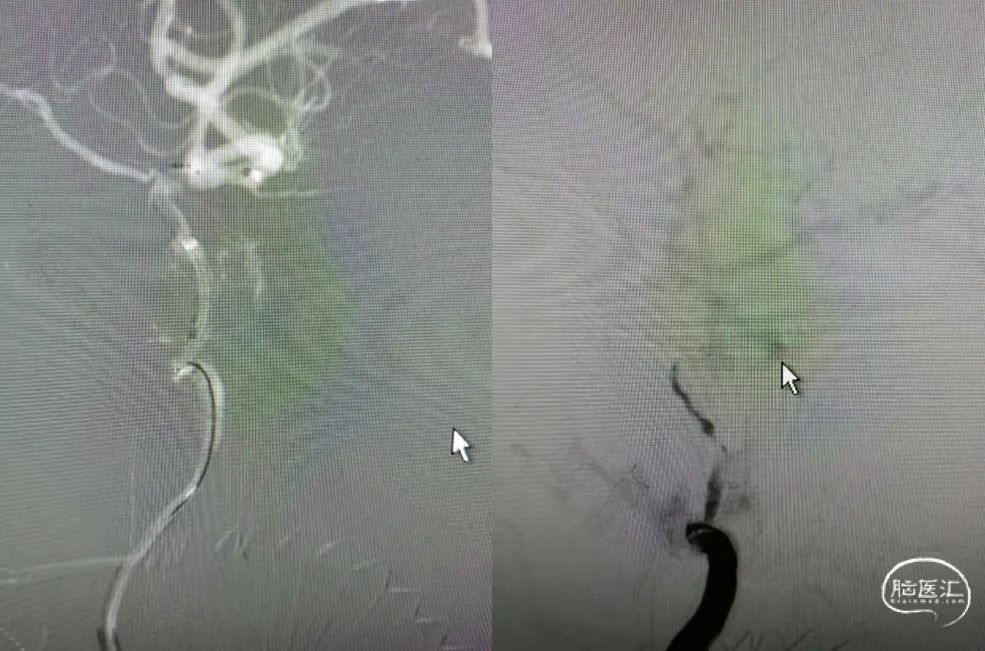

6F-远端通路导管在黑泥鳅导丝的指引下通过闭塞段送至眼动脉段,造影证实闭塞段在海绵窦段,予以ADPAT技术取出少量血栓,仍未开通。

通过微导管释放取栓支架,SWIM取栓技术,可见海绵窦段狭窄,前向血流不稳定。

利用PTA球囊导管对狭窄处进行扩张,可见狭窄明显改善,但眼动脉段以后闭塞,再次将取栓支架予以取栓,可见斑块逃逸至M1段。